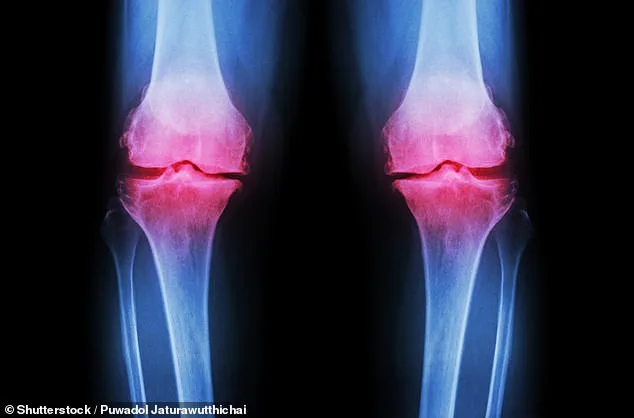

Groundbreaking new knee pain treatment for debilitating joint disease offers hope to 32 million Americans. Scientists have developed a new treatment that involves growing a living human knee in the lab, raising hopes for osteoarthritis patients. Researchers at Columbia University made a 3D-printed scaffold of a knee from biodegradable material, and then added bone and cartilage cells. Over about a year, these cells regenerated the joint's natural cartilage and bone tissues while the scaffold slowly dissolved, creating an entire lab-grown knee. Scientists say this new joint could be transplanted into patients, offering a permanent solution for the agonizing condition. The research is one of the latest breakthroughs that could transform care for patients suffering from osteoarthritis, a debilitating condition where the protective cartilage cushioning the ends of joints gradually breaks down, causing pain, stiffness and loss of mobility. About 32 million Americans suffer from the condition, of which 14 million have knee osteoarthritis, which is also among the leading causes of disability in the US. There is no cure for the condition, and current treatments focus on managing pain via exercises to strengthen muscles, injections, which only ease pain for a few weeks to months, or a full joint replacement, an invasive surgery with considerable painful recovery.

Researchers say they have found a way to grow a living human knee that could be transplanted into patients suffering from osteoarthritis (stock image). At Columbia University, the team has so far created the living joints as a prototype, or an early, preliminary model of the potential treatment option. No testing in live human patients has been conducted yet. Over the next three years, they now plan to move to preclinical and clinical trials. The living knees can be grown using the patient's own stem cells, extracted from abdominal fat, or from donor cells, if the patient has no cartilage, the scientists said. The prototypes have already been implanted into cadavers, the New York Times reports, to test whether they can bear weight and are suitable for walking. The scientists are now planning to implant the knees into large animals, although the species was not named, before they are tested in humans. When the living knees are implanted, researchers say they are linked to the body's blood vessels, allowing them to function normally and like the original knee. It is not clear whether the research could also be used for other joints, including the hips and joints in the feet, that are also affected by osteoarthritis.